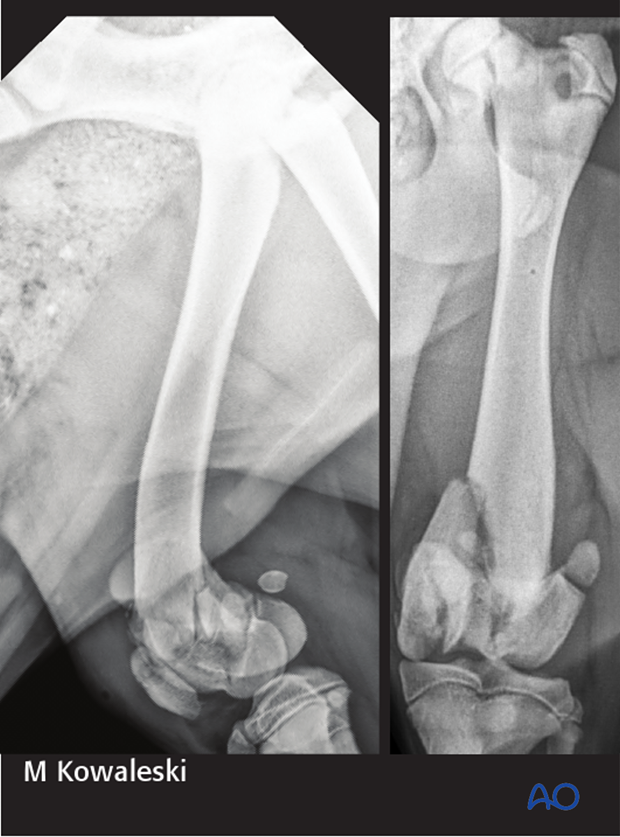

5-month-old Labrador retriever presented for left pelvic limb lameness after jumping out of the window of a moving car, with a 33-C3 fracture of the distal femur, a transverse fracture of the patella, and a 31-B2 fracture.